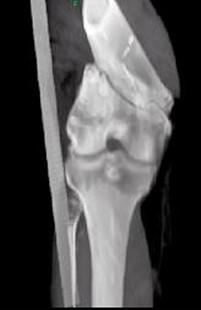

问题 男,45岁,车祸后左膝部剧痛,红肿,不能活动,请结合影像学检查,选出最可能的诊断 ( )

选项 A、胫骨骨折 B、腓骨骨折 C、股骨下端骨折 D、柯莱斯骨折 E、股骨颈骨折

答案 C